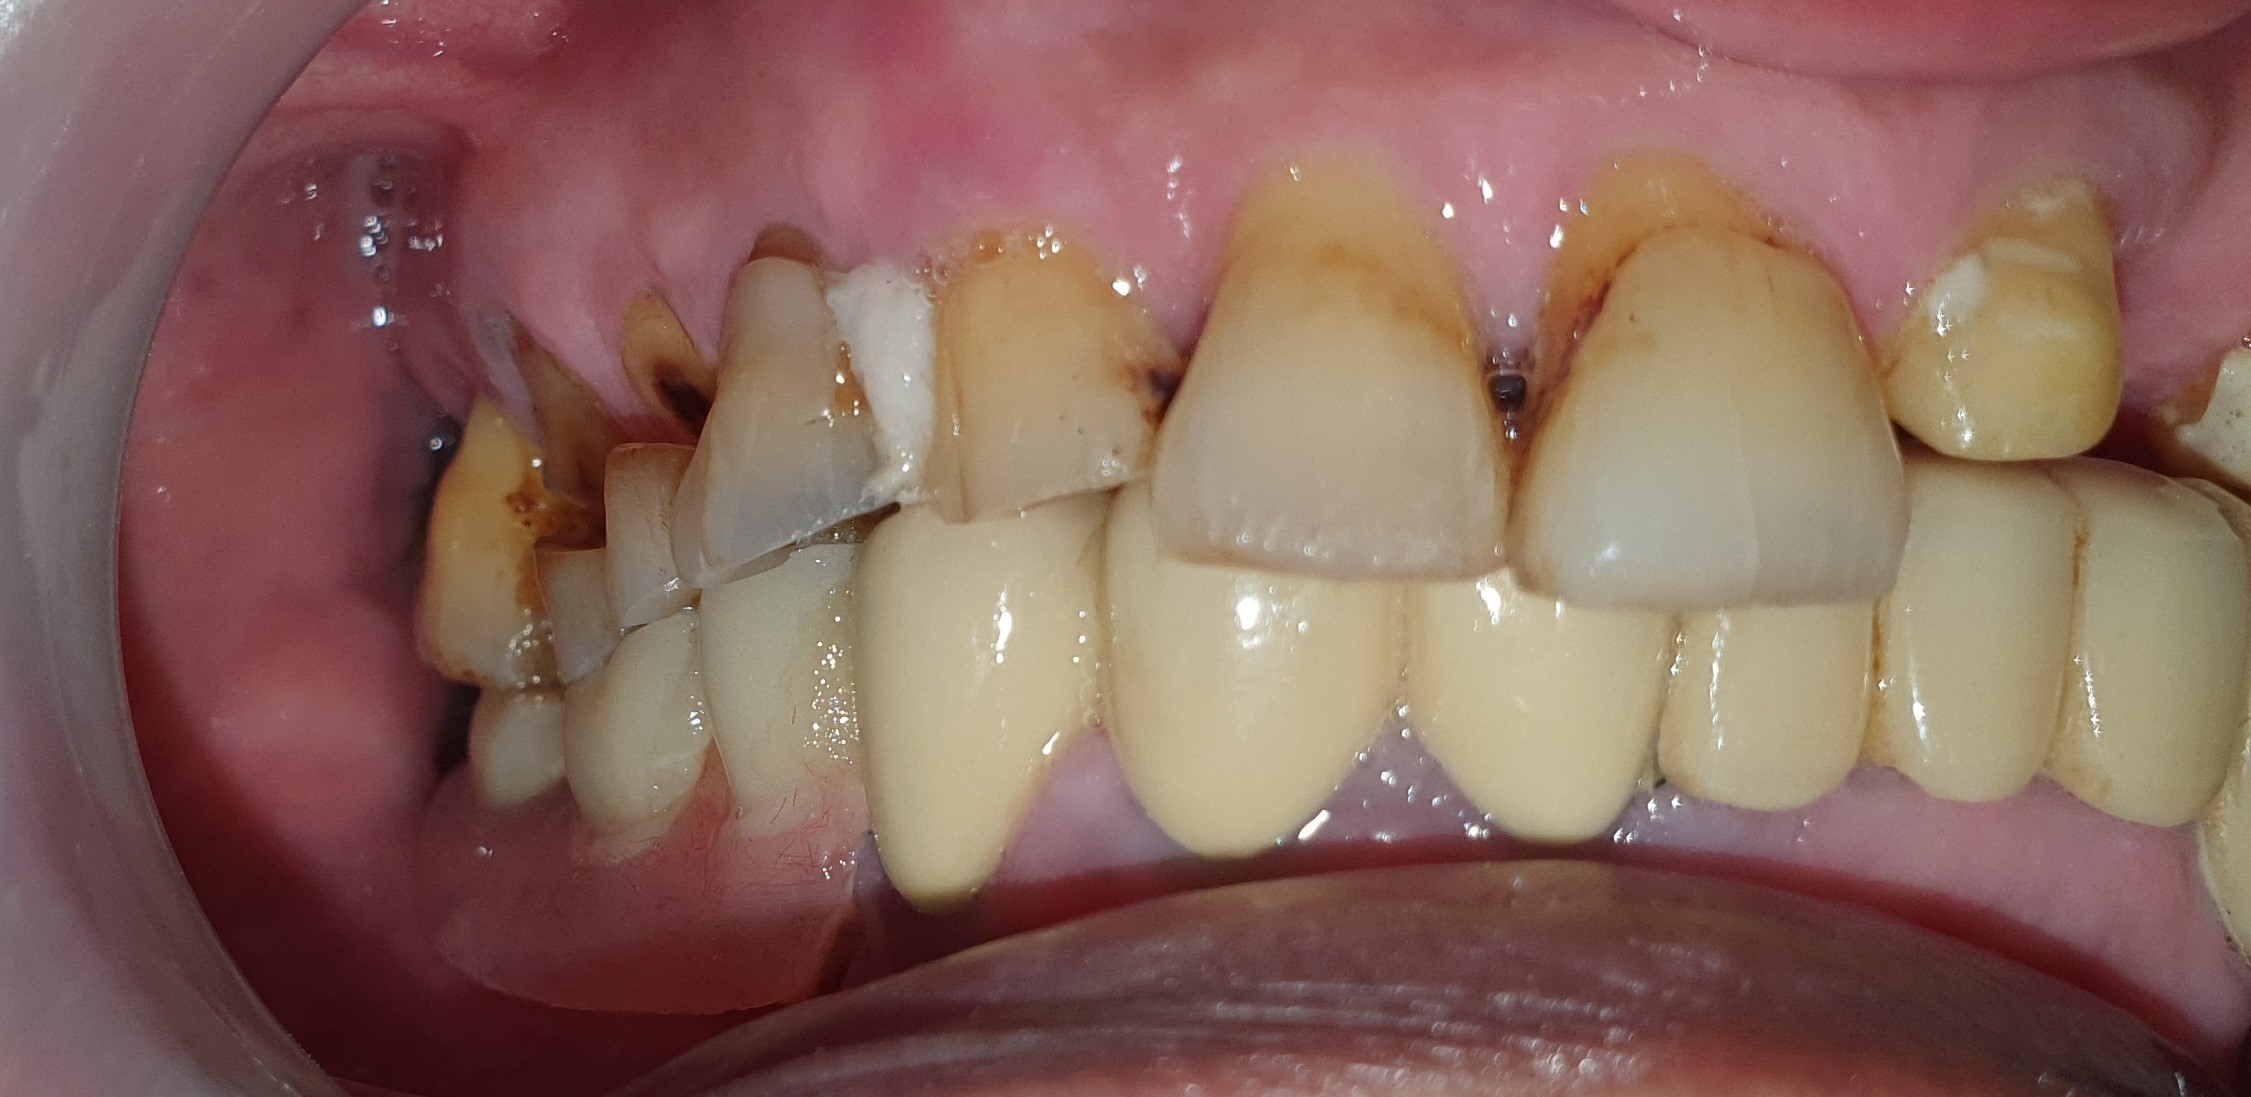

Tình trạng răng ban đầu

Hình ảnh răng hàm trên và dưới

Răng mock-up trên miệng – đồng thời là răng tạm trong quá trình chờ răng sứ